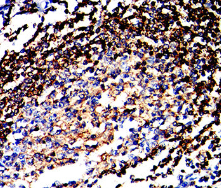

IHC    1/200 - 1/1000